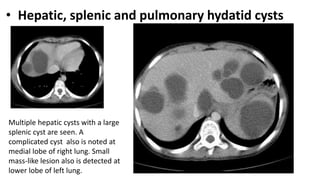

• Hepatic, splenic and pulmonary hydatid cysts

Multiple hepatic cysts with a large

splenic cyst are seen. A

complicated cyst also is noted at

medial lobe of right lung. Small

mass-like lesion also is detected at

lower lobe of left lung.